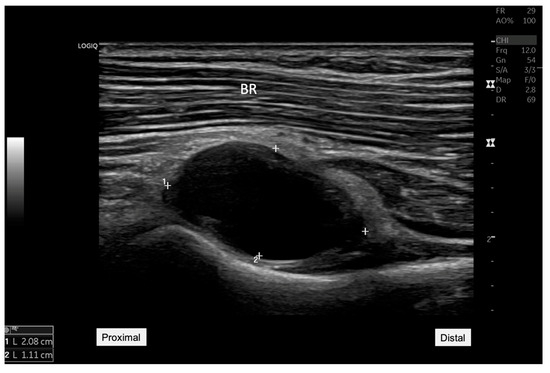

Figure 1. Ultrasound image showing an anechoic cyst measuring 20.8 mm by 11.1 mm located adjacent to the radiocapitellar joint. This finding was critical in reorienting the differential diagnosis toward the possibility of a synovial cyst impacting nearby neural structures. BR: Brachial radialis. A 45-year-old woman presented to our rehabilitation outpatient clinic with a three-week history of persistent pain and weakness in her right elbow and forearm, particularly exacerbated by wrist extension movements. Initial clinical assessments suggested possible lateral epicondylitis [1], but the patient’s lack of response to standard conservative treatments prompted further diagnostic evaluation to explore underlying causes. On physical examination, manual muscle testing revealed significant weakness in right-hand extension involving all five fingers (grade 3 of 5) and wrist extension (grade 3 of 5). However, elbow extension remained strong (grade 5 of 5). Sensory examination revealed no deficits in the right hand or fingers, while the patient reported pain localized to the proximal forearm, notably exacerbated by wrist and finger extension movements. Electrophysiological testing revealed evidence of a conduction block with intact distal compound muscle action potential (CMAP) amplitude, suggesting radial nerve compression. Ultrasound examination was conducted using a GE LOGIQ P8 machine, with a 12-MHz linear transducer, ideal for detailed nerve and superficial soft tissue. Ultrasound imaging revealed a hypoechoic mass, measuring 20.8 mm by 11.1 mm near the radiocapitellar joint (Figure 1). The longitudinal ultrasound view of the radial nerve (Figure 2) illustrates the entrapment of the posterior interosseous nerve (PIN), as it courses through the Arcade of Frohse. Notable compression of the nerve was seen due to an underlying anechoic cyst, which contributes significantly to the PIN’s entrapment at this anatomical site. The cyst’s proximity to the nerve and its effect on the nerve’s appearance and function are critical for diagnosing radial nerve compression. Additionally, nerve tracking to the supinator level also showed distinct hypoechogenicity and swelling of the PIN as it passed through the supinator muscle on the affected side, highlighting the pathological changes consistent with radial nerve compression (Figure 3) [2].